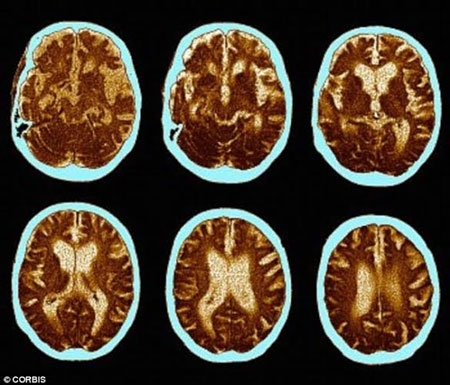

Chúng ta đều biết rằng sự số lượng của tế bào não tỷ lệ nghịch với số tuổi. Thực tế, khi bắt đầu bước vào tuổi 35, mỗi ngày, chúng ta mất 7.000 tế bào não. Đọc thông tin này khiến nhiều người rất lo lắng và bi quan.

| Nghiên cứu của Trường Đại học Princeton cho thấy sex thường xuyên giúp chúng ta sản sinh những tế bào não mới. |

Một nghiên cứu khác được công bố trên tạp chí PLoS ONE cũng cho biết quan hệ tình dục kích thích sự tăng trưởng của các tế bào não ở vùng hippocampus, một phần của não chịu trách nhiệm về trí nhớ và khả năng tiếp thu kiến thức.

Các yếu tố như căng thẳng và trầm cảm có thể thu nhỏ vùng hippocampus, trong khi tập thể dục và quan hệ tình dục lại có tác dụng ngược lại.

“Những người lớn tuổi có ít hoạt động tình dục có nguy cơ mất trí nhớ cao”, Tiến sĩ Ghosh, chuyên gia về sức khỏe tình dục tại Bệnh viện Spire, Liverpool (Anh) cho biết.

Không những thế, chuyện phòng the cũng tăng lưu lượng máu đến não, cải thiện mức độ oxy.

“Quét não bằng kỹ thuật cộng hưởng từ (MRI) đã cho thấy đạt cực khoái giúp các tế bào thần kinh trong não hoạt động mạnh hơn và sử dụng nhiều oxy hơn”, Barry Komisaruk, Giáo sư tâm lý học tại Đại học Rutgers giải thích.